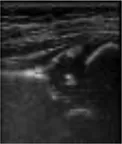

In this study, the GE LOGIQ-E9 ultrasonic diagnostic instrument (America) and 9l linear probe with a frequency range of 5.0–9.0 MHz were employed for imaging of the hip joint. The ultrasound coronal plane of Graf’s method was chosen as the standard imaging technique for this purpose. The imaging procedures were conducted by experienced senior physicians who possess the necessary expertise and technical skills in ultrasound imaging. In the standard imaging, four markers were identified, namely the iliac bone, bony rim point, lower iliac limb point, and glenoid labrum, as illustrated in Figure 2. These markers were selected based on their ability to provide accurate and reliable measurements of the hip joint. The utilization of a standardized imaging protocol and the identification of these markers allowed for consistent and reproducible imaging of the hip joint, ensuring the validity and reliability of the data obtained in this study.

FIGURE 2

www.frontiersin.org

Figure 2. Measurement of the neutral coronal plane of the hip joint using the graf method. (A) Iliac bone, (B) bony rim point, (C) lower iliac limb point, (D) glenoid labrum.